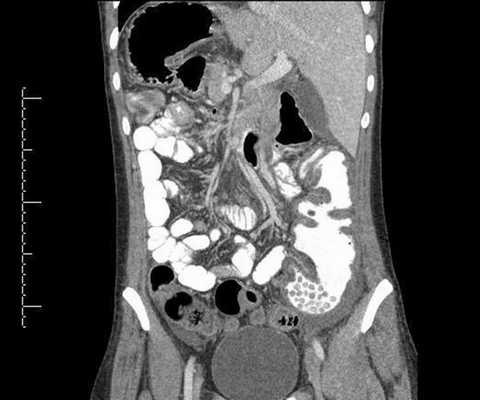

Облучение при КТ брюшной полости

Компьютерную томографию живота проводят с целью дифференциальной диагностики патологий внутренних органов. Чаще назначают комплексное обследование. В результате КТ брюшной полости оценивают состояние:

- печени;

- желчного пузыря с протоками;

- поджелудочной железы;

- селезенки.

Исследование забрюшинного пространства визуализирует строение:

- почек;

- мочеточников (верхнего отдела);

- надпочечников.

Бесконтрастное сканирование занимает до 15 минут. Уровень лучевой нагрузки во время сеанса составляет 5-7 мЗв. При сканировании забрюшинного пространства, области малого таза доза радиации возрастает до 10 мЗв. Рекомендовано проходить комплексную компьютерную томографию живота не более 1 раза в год (за исключением ряда патологий).

МСКТ брюшной полости (достроена фронтальная проекция)